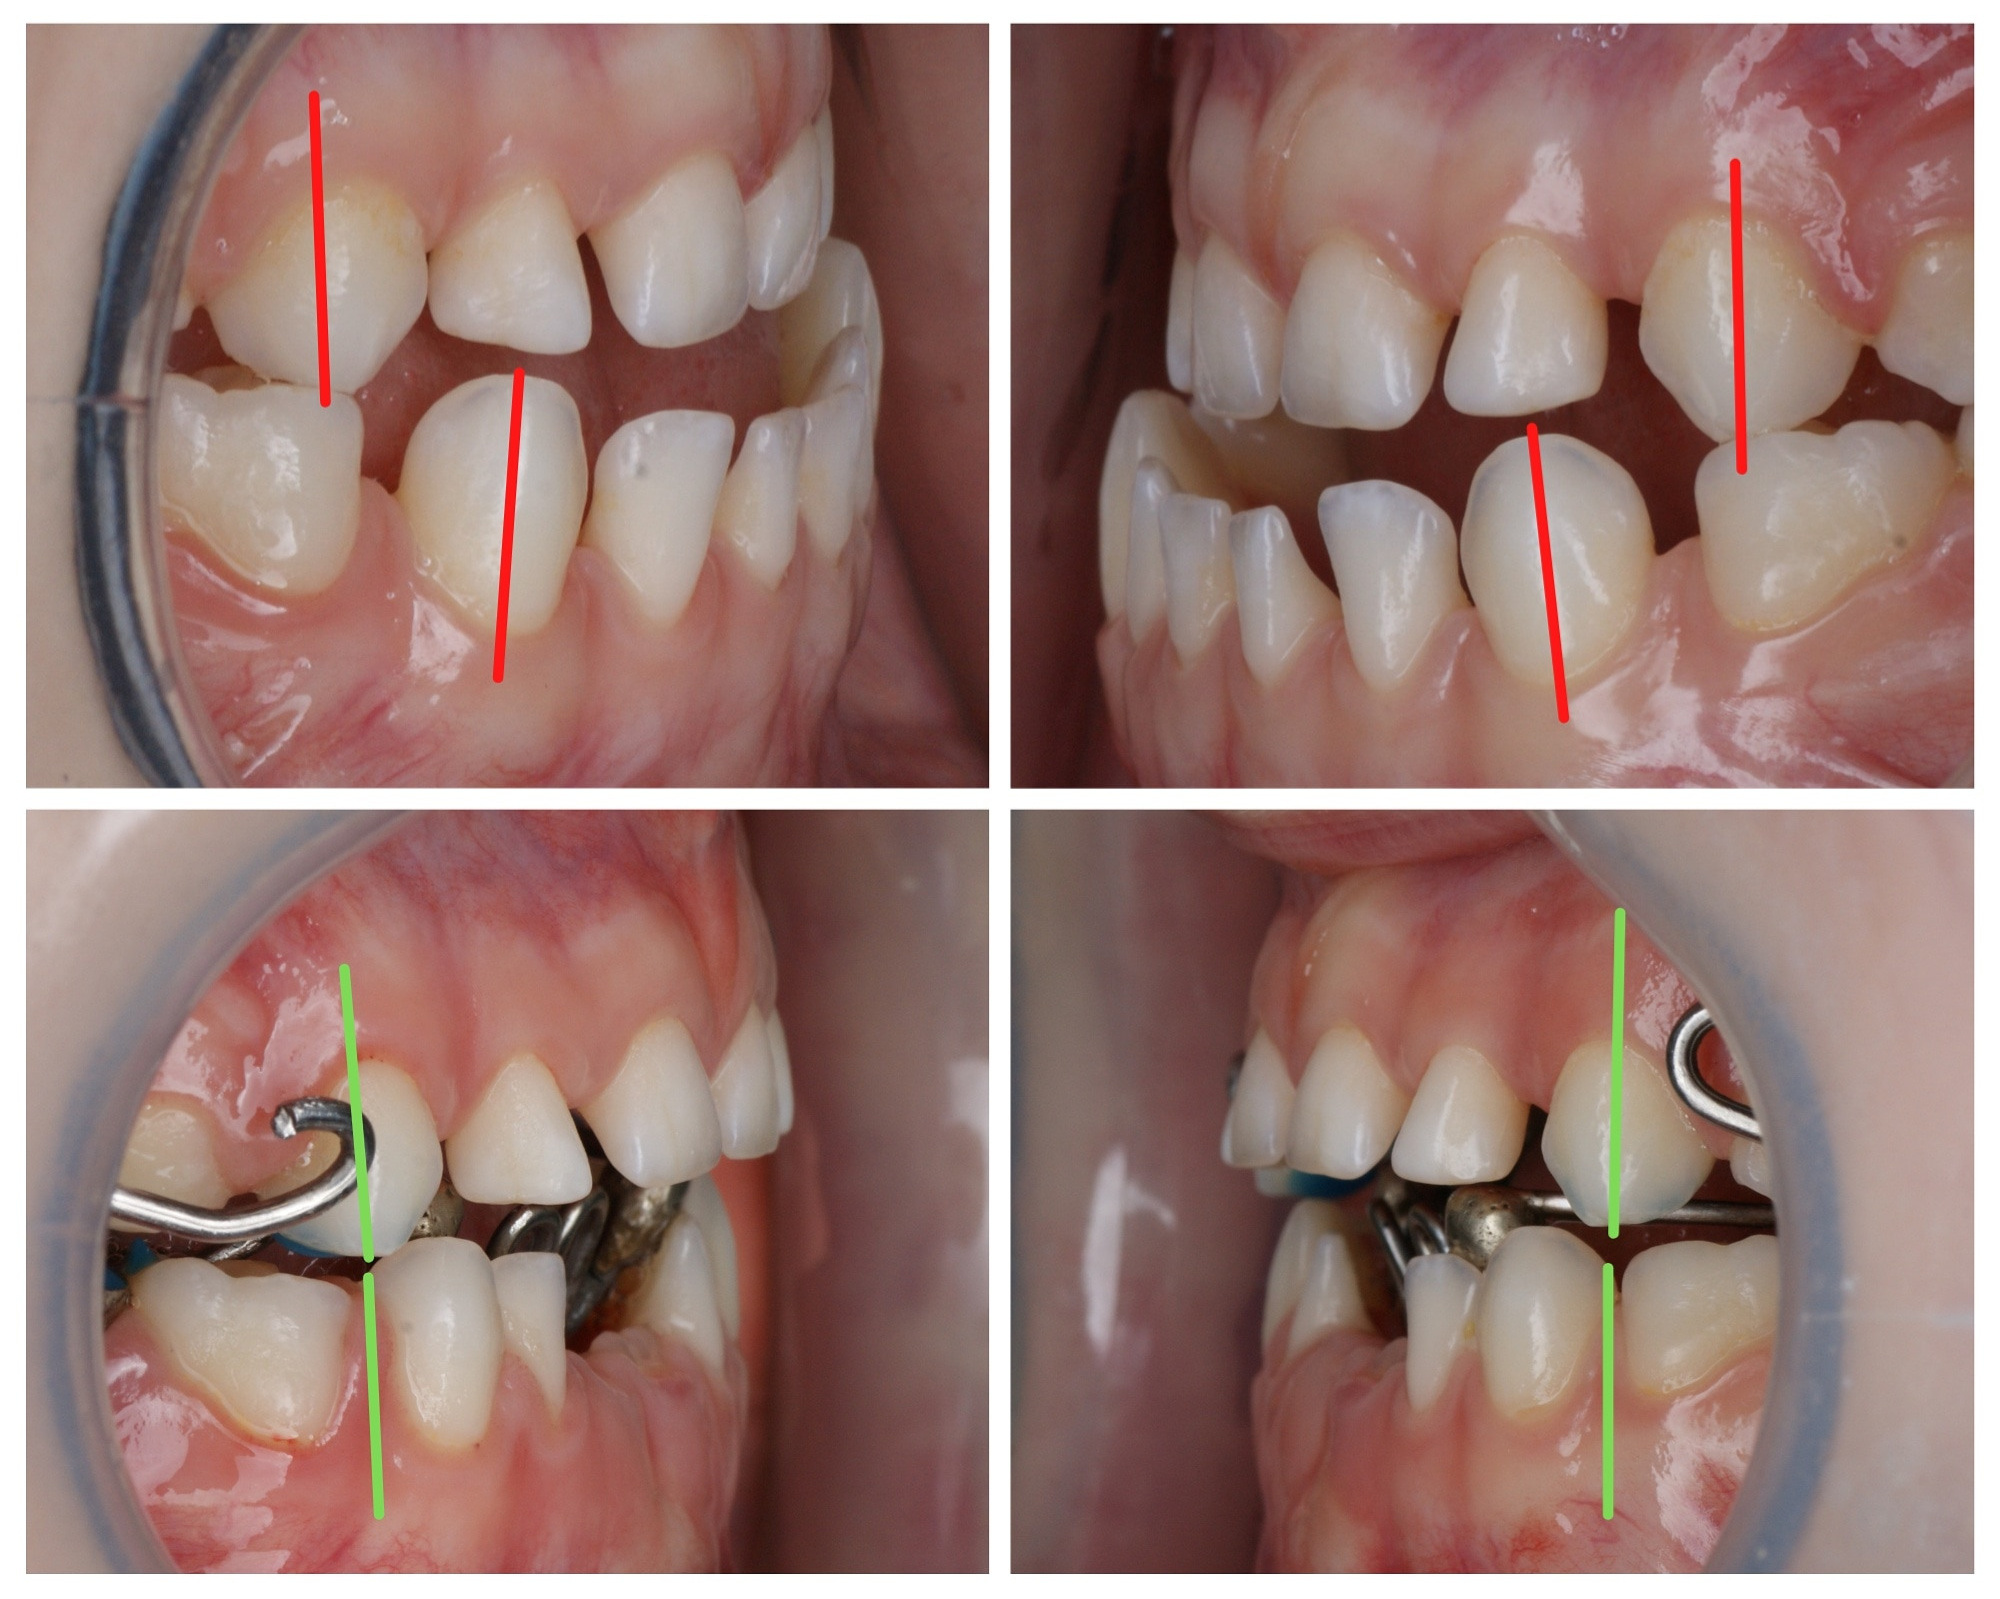

Как должно быть:

1) Широкие промежутки между всеми молочным зубами говорят о хорошем росте челюстей, о том, что запас места для постоянных зубов есть.

2) Наклоны зубов прямые, зубы не вдавлены внутрь, как на первой фотографии. Правильный наклон обеспечивается правильным положением языка и хорошим жеванием.

3) Бугры клыков и боковых зубов, а также режущие края передних зубов должны стираться. Если зубы острые, значит ребёнок не жуёт. Острые бугры блокируют плавные движения челюсти и ограничивают рост. Надеюсь, понятно. ПРОВЕРЯЙТЕ!

Эта фраза знакома многим ответственным родителям, которые привели на приём к ОРТОДОНТУ своего ребёнка в 5-10 лет, заподозрив проблему или понимая, что места постоянным зубам откровенно не хватает! Горькая правда в том, что брекеты - не волшебное средство от всех проблем, они "расставляют" зубы внутри сформированого объёма челюсти, но никак не влияют на её рост. Родители ждут, а тем временем драгоценное время, когда ребёнок растёт, уходит... Во взрослом возрасте приходится удалять здоровые зубы или прибегать к ортогнатической хирургической операции. 📸 На фото узкая нижняя челюсть, места постоянным зубам нет, боковые резцы прорезываются "вторым рядом".